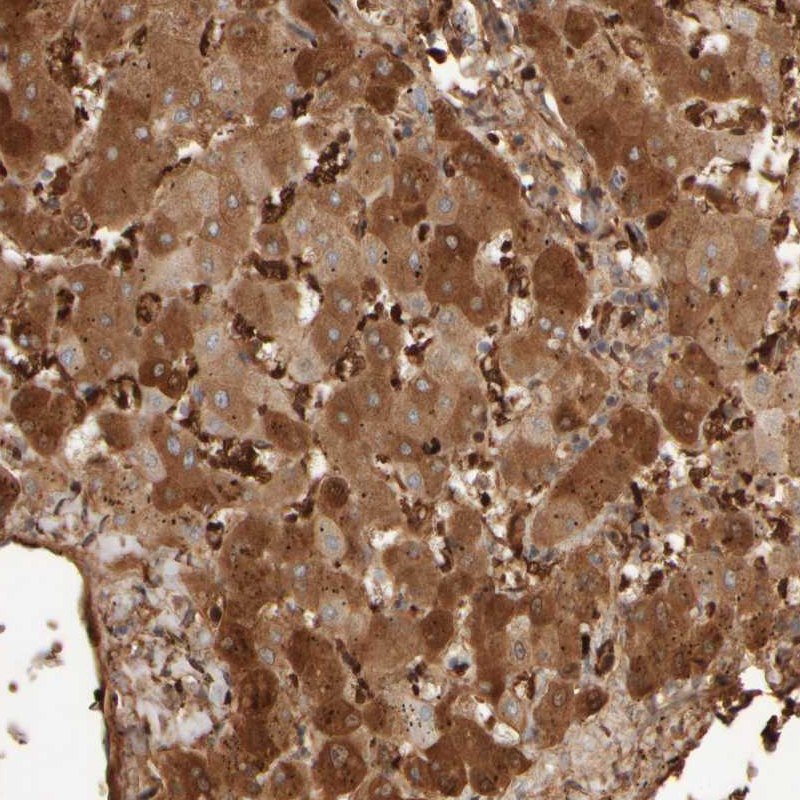

Immunohistochemical staining of human liver shows strong cytoplasmic positivity in hepatocytes.